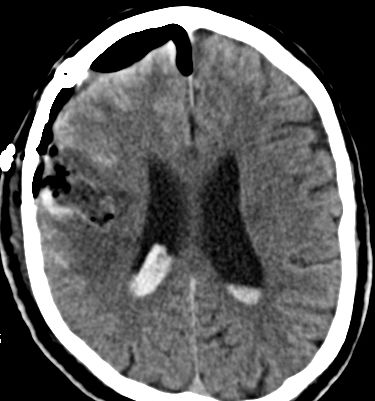

Als diagnostische Maßnahme wird in der Regel ein craniales Computertomogramm (CCT) durchgeführt. Intrazerebrale Blutungen lassen sich mit dieser Methode sicher diagnostizieren.

Je nach Lokalisation und Ausdehnung der Blutung und in Abhängigkeit vom klinischen Zustand des Patienten muss entschieden werden, ob eine chirurgische Intervention notwendig ist. In diesem Falle wird über eine Eröffnung der Schädeldecke die Blutung in mikrochirurgischer Technik entfernt.

Bild einer intracerebralen Blutung nach OP.

Bild einer intracerebralen Blutung vor OP.